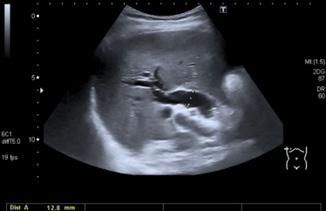

Figura 12. Una delgada membrana semilunar se proyecta hacia la luz en la parte superior del esófago, junto con la anemia por deficiencia de hierro (coiloniquia) y la disfagia forman parte de la tríada clásica del síndrome de Plummer-Vinson. Figura 13. Trastornos motores del esófago. A: Acalasia; B: Espasmo difuso del esófago; C: Esclerodermia Figura 14 Cáncer de esófago produce disfagia mecánica progresiva con baja de peso significativo

♦ Radiografía baritada: imagen en pico de pájaro o punta de lápiz

♦ Radiografía baritada: imagen en sacacorcho

♦ Radiografía baritada: imagen en tubo rígido